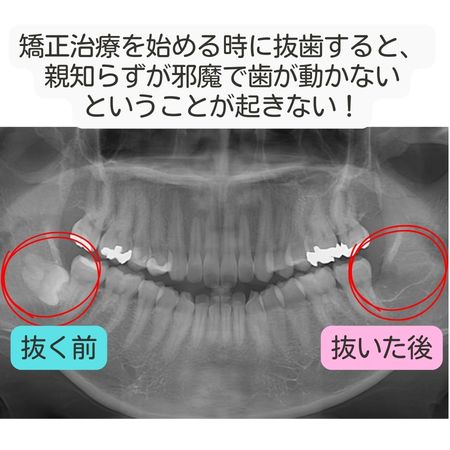

矯正治療を検討する際、もっとも多く選ばれるのが「矯正前に親知らずを抜く」ケースです。

これは単に慣習ではなく、治療計画を立てやすくし、矯正をスムーズに進めるうえで合理的な理由があります。

なぜ矯正前に抜くことが多いのか

矯正前に親知らずを抜く最大の理由は、歯を動かすためのスペースと自由度を確保するためです。

たとえば、

- 奥歯を後方に下げたい

- 歯列全体をバランスよく並べたい

といった場合、親知らずが残っていると、歯の移動が制限されることがあります。

また、矯正装置の設計上も、

- 親知らずがあることでワイヤーやマウスピースの計画が複雑になる

- 治療途中で「やはり抜いたほうが良い」と判断が変わる

といった事態を避けやすくなります。

最初から抜歯を済ませておくことで、矯正計画を一貫した流れで進めやすくなる点が、矯正前抜歯が選ばれる大きな理由です。